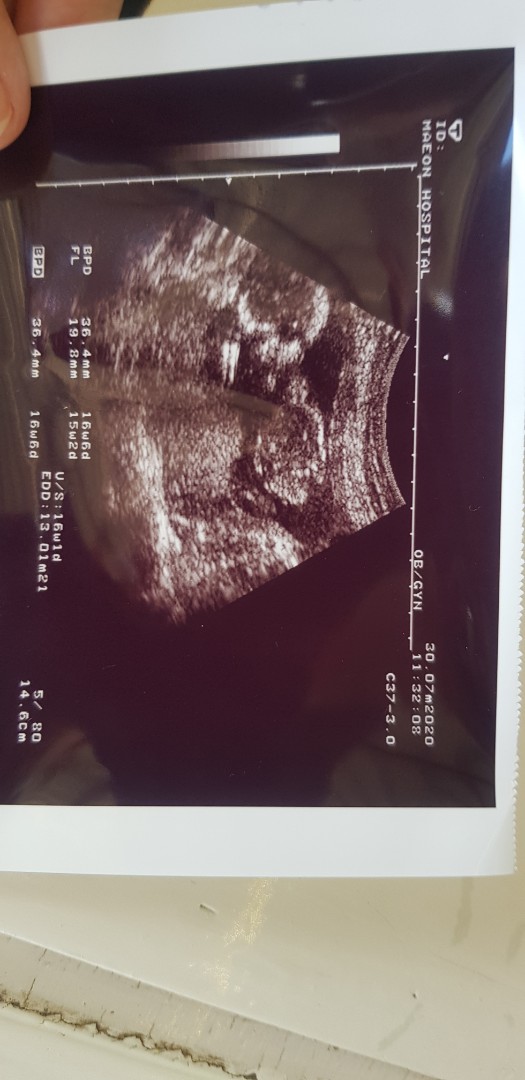

สอบถามอายุครรภ์ 3 เดือนค่ะ

ไปอัลตราซาวด์แล้วลูกไม่ดิ้นเลยค่ะนิ่งไปเลย แต่หัวใจเต้นปกติ หมอบอกทุกอย่างปกติแต่เด็กอาจจะหลับ บ้านอื่นตอนไปอัลตราซาวด์เป็นเหมือนกันบ้างมั้ยคะ แม่อดดูหนูดิ้นเลย ต้องรอเดือนหน้าค่ะ 😬😬